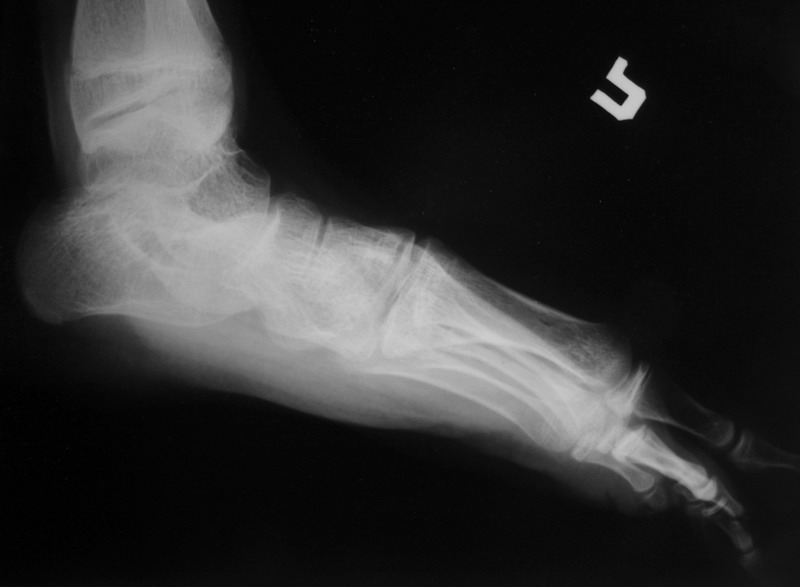

Пациент 15 л., болезнь Литтля, спастический нижний парапарез, интеллект высокий. Ребенок настроен на активный образ жизни. С недавнего времени начал ходить без дополнительной опоры. Появилась проблема с левой стопой - во время ходьбы опора приходится на смещенную кнутри таранную кость.

Стандартным хирургическим вмешательством в таком случае действительно является костнопластический корригирующий трёхсуставной артродез, вероятно с мягкотканным компонентом (эквинус). Такие операции без риска нарушения роста стопы можно выполнять с 12-летнего возраста. Так, что у Вашего пациента никакой опасности нет. Делать это можно где угодно по желанию родителей. Но, может быть не кидаться сразу за границу. У нас специалисты не хуже (а, может быть и лучше). Это и институт Турнера под С-Пб, и 18-я неврологическая больница в Москве (А.М.Журавлёв). Делаем такие операции и мы. Важный момент: после операции необходим полноценный специальный курс реабилитационного лечения, ортопедические пособия и наблюдение.

В приводимом случае, 15 летнему больному показан 3-суставной артродез. Однако считаю нецелесообразным существенно менять конфигурацию стопы, поскольку плоско-вальгусные деформации стоп это компенсаторный ответ на сгибательно-приводящие установки нижних конечностей. Изменение положения стоп(коррекция пронации) может нарушить сложившийся стереотип ходьбы, и ухудшить ситуацию.

1. in spastic flat foot deformity which is not fixed but passively stretchable in a normal position it´s possible to perform the calcaneal lengthening (Evans)

2. in fixed spastic flat foot in adolescent and adults you have to perform the correctice triple arthrodesis.

This is typical deformity for spastic diplegia in CP .In 15 years old boy the best option is tripple arthrodesis .